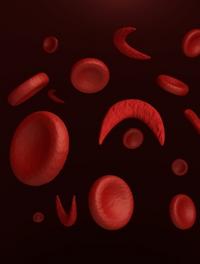

L'étude randomisée contrôlée de phase 3 HOPE a évalué l'impact du voxelotor versus placebo sur le cours évolutif de la drépanocytose [...]

Cent millions de personnes dans le monde souffrent de drépanocytose. Le mécanisme physiopathologique de la vaso-occlusion est complexe, [...]